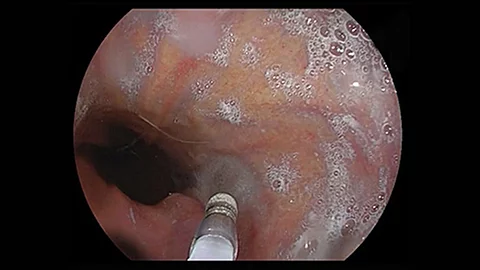

Endoskopisches LehrvideoNadelmesser-Precut-Sphinkterotomie

Ob eine Papille einfach oder schwierig zu kanülieren ist, kann man ihr ad hoc nicht ansehen. Im Falle dieser Papille musste eine Precut-Sphinkterotomie erfolgen, da mehrere Kanülierungsversuche gescheitert sind. Welche Schritte man dabei beachten sollte, erklärt PD Dr. Jochen Weigt anschaulich im neuen Video.